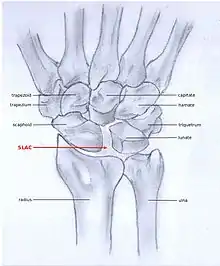

SLAC and SNAC are two patterns of wrist osteoarthritis, following predictable patterns depending on the type of underlying injury. SLAC is caused by scapholunate ligament rupture, and SNAC is caused by a scaphoid fracture which does not heal non-union.

SLAC is more common than SNAC; 55% of the patients with wrist osteoarthritis have a SLAC wrist.[3]

SLAC

Scapholunate advanced collapse (SLAC) is a predictable pattern of wrist osteoarthritis that results from untreated long-standing scapholunate ligament rupture and the associated carpal malalignment.[4] The misalignment is described as dorsal intercalated segment instability (DISI) which is where the lunate angulates towards the dorsal side of the hand.[2][5]

Because SLAC results from scapholunate ligament rupture, there is a larger space between the two bones, also known as the Terry Thomas sign.[10] Scaphoid instability due to the ligament rupture can be stactic or dynamic.[11] When the X-ray is diagnostic and there is a convincing Terry Thomas sign it is a static scaphoid instability. When the scaphoid is made unstable by either the patient or by manipulation by the examining physician it is a dynamic instability.[11]